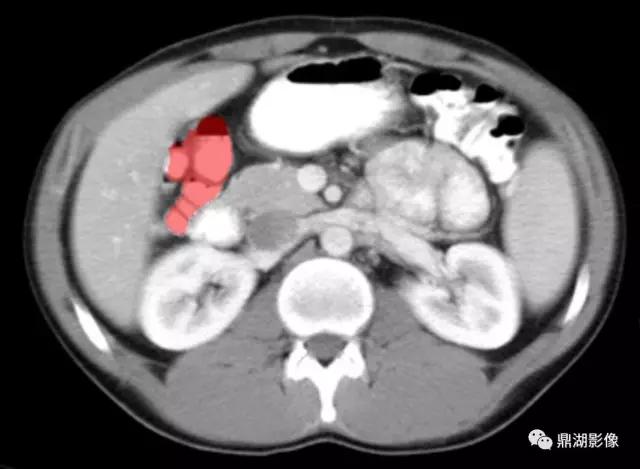

肝曲(Hepatic Flexure)

脾区(Splenic Flexure)

脾静脉(Splenic Vein)